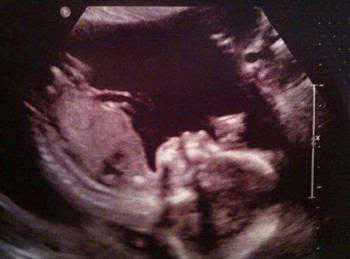

从医学角度看,宝宝处在不断发育和运动中,宝宝周围的胎盘组织(羊膜、叶状绒毛膜和底蜕膜)会随着胎儿的运动发生位置改变,在加上拍照角度的影响,所以才会拍出恐怖的象形化胎儿照片。为此幸孕姐特意收集了以下会让父母心情一下从天堂掉到地狱的恐怖超声波照——

照片中,胎儿已初具人形,而右上角的胎盘等组织,看上去像是一个阴森恐怖的“恶魔”正在母亲子宫外注视着这个胎儿。